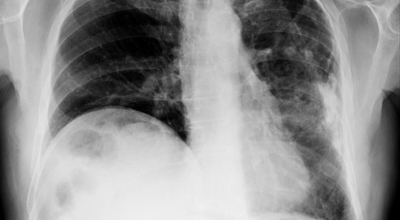

흉부 엑스레이

엑스레이 검사 방법으로는 실제 크기로 촬영하는 흉부 직접 촬영과 마이너스 70mm, 100mm 사진으로 촬영하는 간접 촬영이 있다고 하며, 일부 사람을 단체로 검사할 때 간접 촬영이 많이 활용돼요. 조사결과에 근거하면 결핵은 과감염성 결핵과 재활성성 결핵으로 구분되며, 기존 결핵은 소아결핵과 성인결핵으로 소속되는 경우가 많았어요. 인간면역결핍바이러스(HIV)에 감염된 사람들은 주로 과감염된 결핵을 보이 다고 알려져 있답니다.

임상적으로 의심스럽긴 하지만 흉부 X선만으로 결핵을 진단하기 어려울 때는 컴퓨터단층촬영(CT)이 유용해요. CT는 오래된 섬유화 병변과 새로운 활성화 병변을 구별하는 데 도움이 되고, 보통과 다르게 작은 기관지나 작은 기관지 주변의 병변은 결핵이 시작된다는 것을 특징으로 제시한다('나무 싹 패턴'). 그리고 CT는 충치진단, 흉곽림프절질환, 결핵(세균성 결핵이 전신에 퍼져 가지가지 장기에 염증을 유발한다), 기관지확장, 기관지협착, 흉막질환 등에 대한 민감도가 높아 결핵에 석회의 침전이 있는지 여부를 판단하는 데 아주 유용해요.